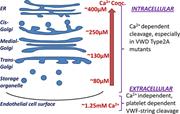

PLATELETS AND THROMBOPOIESIS

THROMBOSIS AND HEMOSTASIS